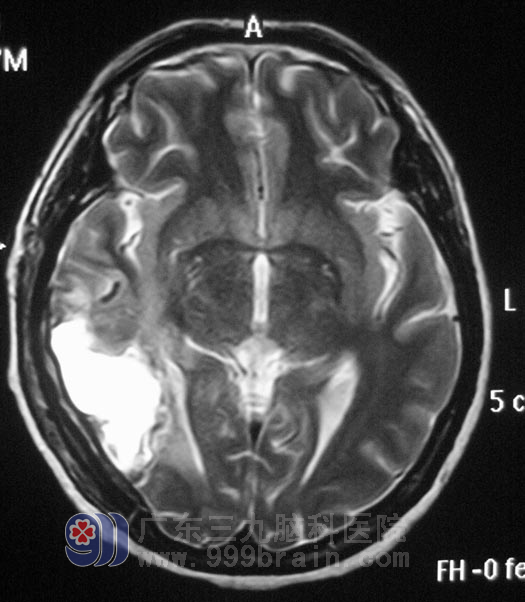

经过一段时间的治疗,5月27日,由鲁明主任主刀,在全麻下行右侧颞枕动静脉畸形切除术+血肿清除术,手术过程顺利。术后杨老师的肢体运动、言语功能以及视觉功能均没有影响,6月6日办理了出院手续。

▲手术后